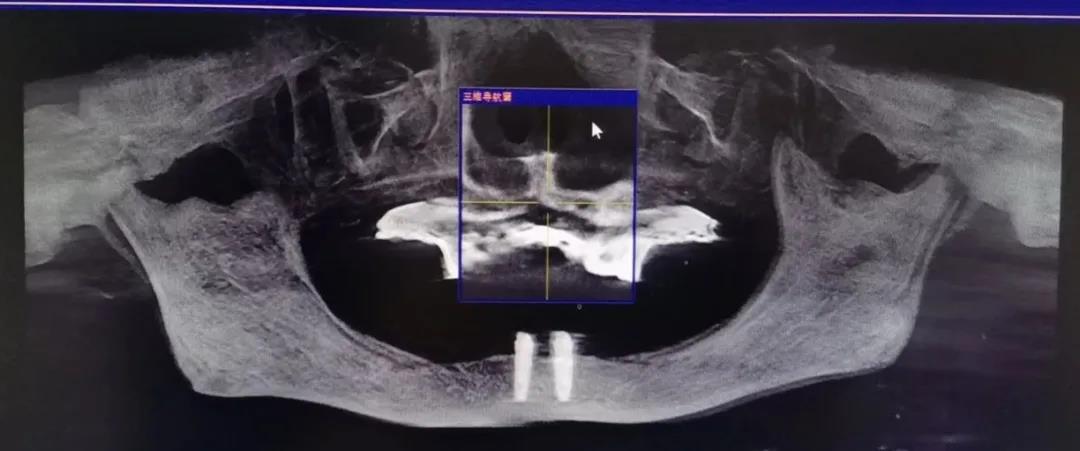

借助德国数字化Sirona CBCT设备,只需要静静地站在设备前等待2分钟左右,就能够迅速获取口内数据,直观了解自己的牙齿内部是否存在问题。

相较于传统的二维X光影像,通过Sirona CBCT重建后我们可以得到三维口内图像。

它的出现彻底改变了传统口腔颌面放射学设备仅能提供二维图像的历史,可以三维显示病变结构,大大提高了诊断能力。

▲ CBCT可以得到三维图像,更加精准

医生可以从任意角度观察分析病例,如缺牙区牙槽骨吸收程度、余留牙是否有炎症等需要先进行治疗以避免干扰种植手术的问题。